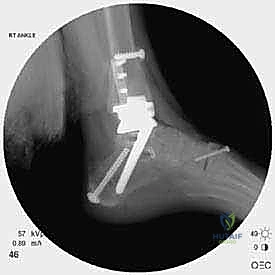

مراجعة مفصل الكاحل الصناعي هي إجراء جراحي ضروري لمعالجة المشاكل التي قد تنشأ بعد الجراحة الأولية، مثل كسور الكعبين أو عدم استقرار المفصل. يتضمن العلاج التشخيص الدقيق عبر الأشعة السينية والتصوير المقطعي، يليه التدخل الجراحي لتثبيت الكسور واستعادة وظيفة الكاحل، مع التركيز على التعافي المبكر.

تُعد جراحة مراجعة مفصل الكاحل الصناعي (Revision Total Ankle Replacement) من الإجراءات الجراحية المتقدمة والبالغة الدقة في عالم جراحة العظام الحديثة. لا تقتصر هذه الجراحة على مجرد استبدال مفصل تالف بآخر جديد، بل هي عملية إنقاذ معقدة للغاية تهدف إلى معالجة المشاكل الميكانيكية والبيولوجية التي تنشأ بعد الجراحة الأولية. من أبرز هذه المشاكل: الفشل الميكانيكي للمفصل، تحلل العظام (Osteolysis)، أو حدوث كسور معقدة في الكعبين (Malleolar Fractures) المحيطة بالمفصل الصناعي. يتطلب هذا الإجراء تقييماً سريرياً وشعاعياً دقيقاً يشمل التصوير المقطعي ثلاثي الأبعاد والأشعة السينية، يليه تدخل جراحي دقيق لاستعادة التوازن الحيوي والميكانيكي للكاحل والحفاظ على الطرف من البتر أو الدمج.

- الأشعة السينية مع تحميل الوزن (Weight-bearing X-rays): لتقييم الزوايا الميكانيكية وتحديد مدى هبوط المفصل أو وجود كسور في الكعب.

علاج هذه الكسور يتطلب مهارة فائقة من الدكتور محمد هطيف، حيث يتم استخدام تقنيات الجراحة الميكروسكوبية وتثبيت الكسور باستخدام صفائح معدنية دقيقة ومسامير (Locking Plates) دون المساس بثبات المفصل الصناعي، أو يتم دمج علاج الكسر ضمن عملية مراجعة المفصل الكلية إذا كان المفصل نفسه تالفاً.

يتم إدخال المفصل الجديد المخصص للمراجعة، والذي يحتوي غالباً على سيقان (Stems) تدخل عميقاً في عظمة الساق وعظمة الكاحل لضمان الثبات الميكانيكي. في حال وجود كسور في الكعب، يتم تثبيتها في هذه المرحلة.